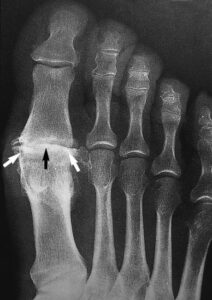

This X-ray reveals osteoarthritis in the metatarsophalangeal joint of the big toe. Joint space narrowing (black arrow) and bone spurs (white arrows) can be seen.